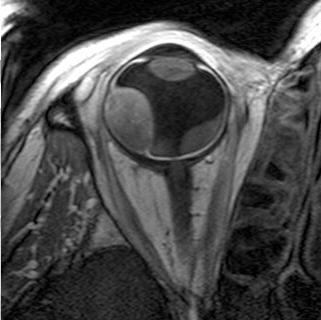

In bestimmten Fällen kann der Augenarzt eine ergänzende Kernspintomographie des erkrankten Auges anfordern. Für diese Untersuchung wird das Auge des Patienten lokal betäubt. Nach erfolgter Betäubung wird der Patient mit einem Krankentransport von der Augenklinik des Klinikums Benjamin Franklin in das speziell ausgerüstete MRT-Labor des Virchow-Klinikums gefahren. Die Untersuchung dort nimmt etwa eine Stunde in Anspruch. Anschließend bringt der Transport den Patienten in die Augenklinik zurück. Falls der Patient zu diesem Zeitpunkt bereits entlassen worden ist, erfolgt die Untersuchung ambulant und ein erneuter stationärer Aufenthalt ist nicht erforderlich.

Für die Kernspinuntersuchung spielt es keine Rolle, ob zuvor Markierungsplättchen aufgenäht worden sind oder nicht. Abgesehen von ihrem unbestrittenen diagnostischen Wert hat sich die Kernspintomographie als klinisch fundierte Grundlage für die sich anschließende Bestrahlungsplanung sehr bewährt. Dies gilt besonders für hochragende oder unregelmäßig geformte Tumoren, aber auch für solche, die mit den herkömmlichen Untersuchungsmethoden ansonsten schlecht einsehbar bzw. schwer abgrenzbar sind.